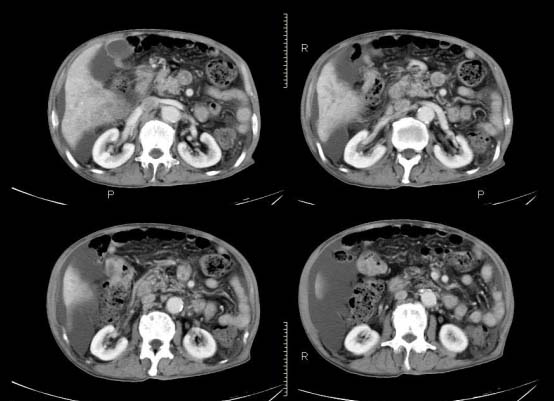

以下是引用杀毒软件在2010-3-30 18:11:00的发言:[br]考虑---hcc侵犯侵犯周围组织〔胰腺、胆管、肠系膜上动静脉〕伴门脉、下腔静脉癌栓形成、动-静脉瘘、肝门、腹腔动脉周围淋巴结转移可能性大、腹水。

以下是引用pujunzhi在2010-3-31 8:45:00的发言:[br]支持 肝癌并多发肝内转移,胰头、肝门、腹腔动脉周围淋巴结转移,下腔静脉癌栓形成,肝硬化、腹水。

以下是引用jsgdoctor在2010-3-30 20:42:00的发言:[br]考虑---hcc侵犯侵犯周围组织〔胰腺、胆管、肠系膜上动静脉〕伴门脉、下腔静脉癌栓形成、动-静脉瘘、肝门、腹腔动脉周围淋巴结转移可能性大、腹水。